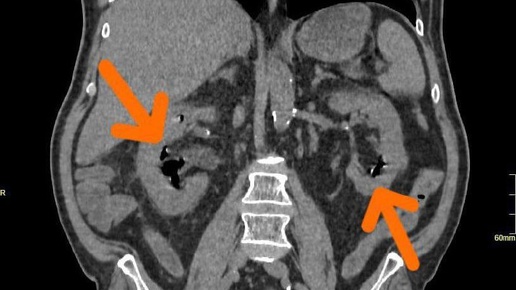

🧠 Когда медицина превращается в детектив. В отделение больницы №52 в Москве доставили пациента, балансирующего на грани жизни и смерти: температура под 40, давление падает, почки отказывают, сепсис набирает обороты. На КТ — картина, от которой даже опытные врачи делают паузу. Газ внутри почек. Эмфизематозный пиелонефрит IV класса — диагноз, который в 9 случаях из 10 заканчивается летально. 🩸 Возбудители — E. coli и Klebsiella. В норме безобидные, но в условиях диабета и нарушенного кровоснабжения почечной ткани они начинают разлагать глюкозу с образованием газа...